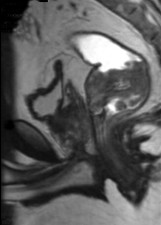

[单选题]男,21岁,下腹部一囊性肿块,无压痛,请结合图像,选择最可能诊断()A.盆腔脓肿B.结肠重复畸形囊肿C.神经纤维瘤D.神经鞘瘤E.间质瘤